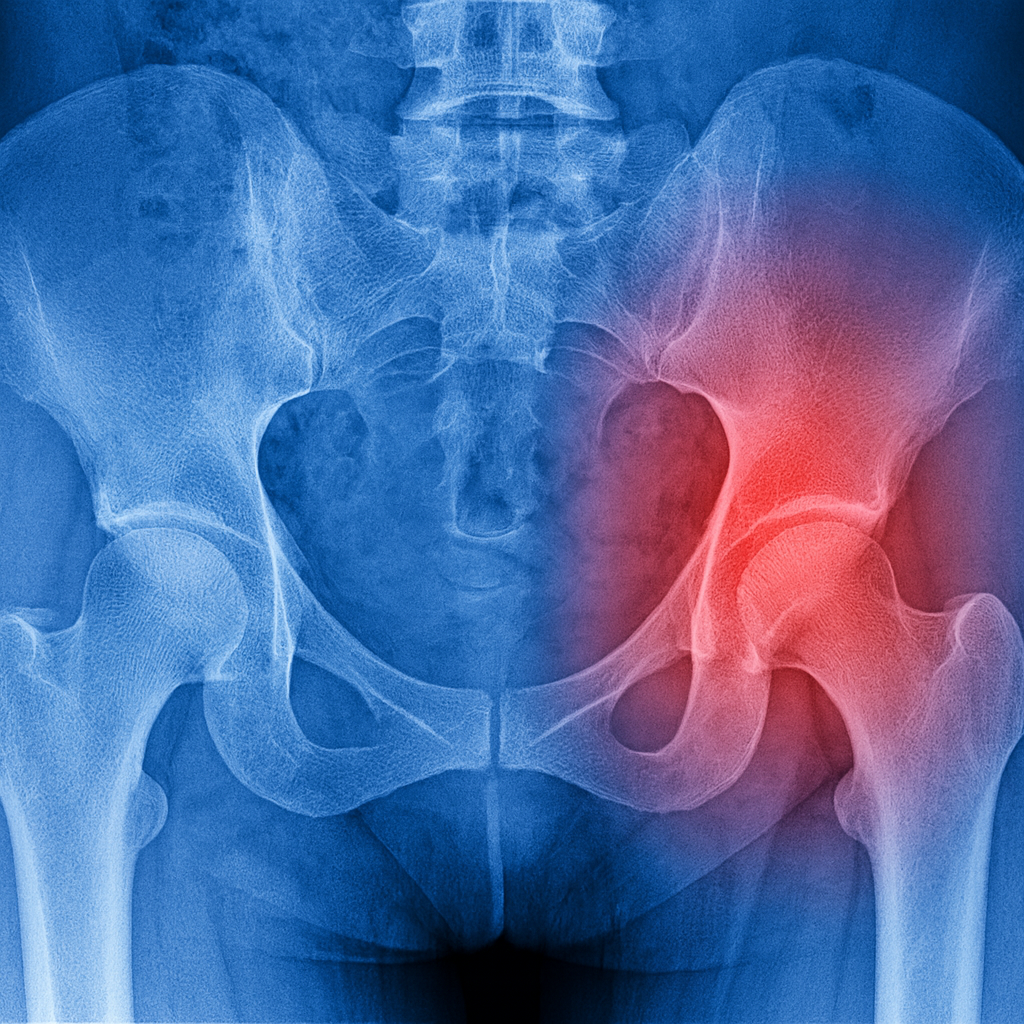

Radiografía de cadera mostrando zona de dolor e inflamación articular